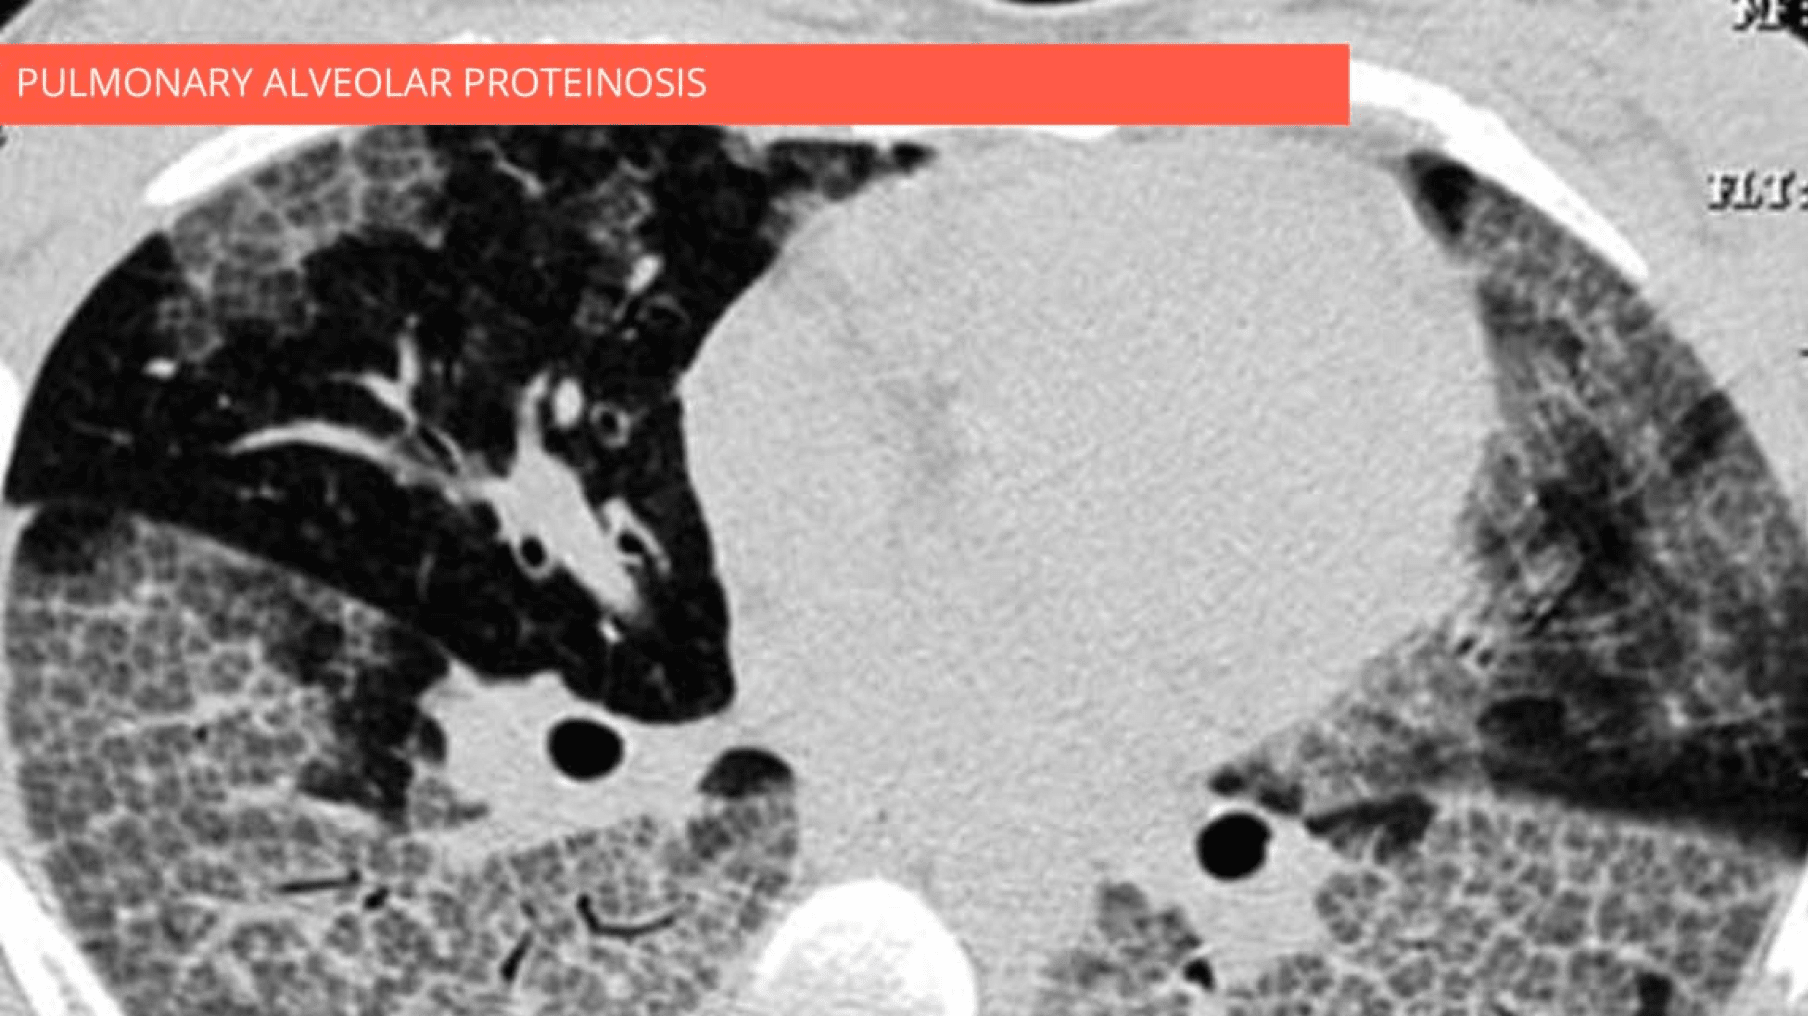

Ground-glass opacity with crazy paving pattern

•  Combination of ground-glass opacity, thickened polygonal septal lines, and intralobular reticulation

• pulmonary alveolar proteinosis ++

Combination of ground-glass opacity, thickened polygonal septal lines, and intralobular reticulations predominantly in the lower lobes. Note the spatial heterogeneity of lesions.